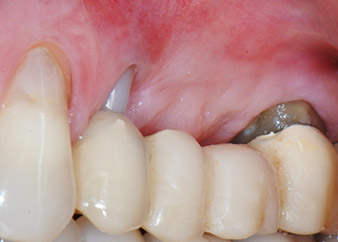

Two-months interim result

Figures 17 and 18 show the clinical result two months after the surgery. Tooth 24 exhibited reduced mobility of Miller class 1, and the soft tissues were free of inflammation. Probing was avoided at this point of time to prevent reinfection and to avoid violating the epithelial attachment. A control visit was scheduled for reentry and placement of healing abutments, six months after the insertion of the implants.

Two months after the surgery, the patient was pain-free.

At the two-months recall, the mobility of the remaining “dental element” 24 was already reduced from Miller 2 to Miller 1. The soft tissue attachment was on the level of the neighbouring tooth 23. Moreover, there were no endodontic or periodontal symptoms, so its prognosis may have to be readjusted.

However, as most of the buccal and proximal bone is missing and the composite build-up extends to the apical section of the root, a higher reattachment level is not to be expected due to biologic reasons (Sculean et al., 2008).